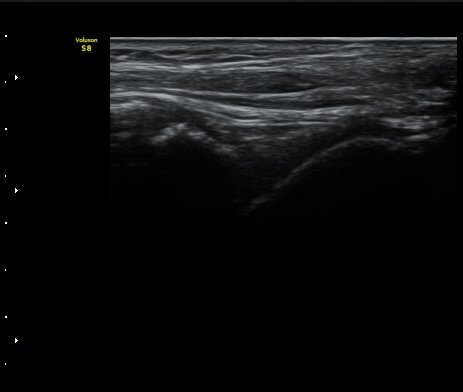

ÃÊÀ½ÆÄÅõ½ÃÇÏ ºÎÇϰ˻翡¼­ ºñ°ñ°ú °ß¿­°ñÀý °ñÆí»çÀÌ¿Í ºñ°ñ°ú °Å°ñ »çÀ̰¡ ¹ú¾îÁø´Ù

(樨毢 1)

ÃÊÀ½ÆÄ Åõ½ÃÇÏ ºÎÇϰ˻翡¼­ ºñ°ñ°ú ÀδëºÎÂøºÎ¿Í  ºñ°ñ°ú °Å°ñ»çÀ̰¡ ¹ú¾îÁöÁö ¾Ê´Â´Ù

(樨毢 2).